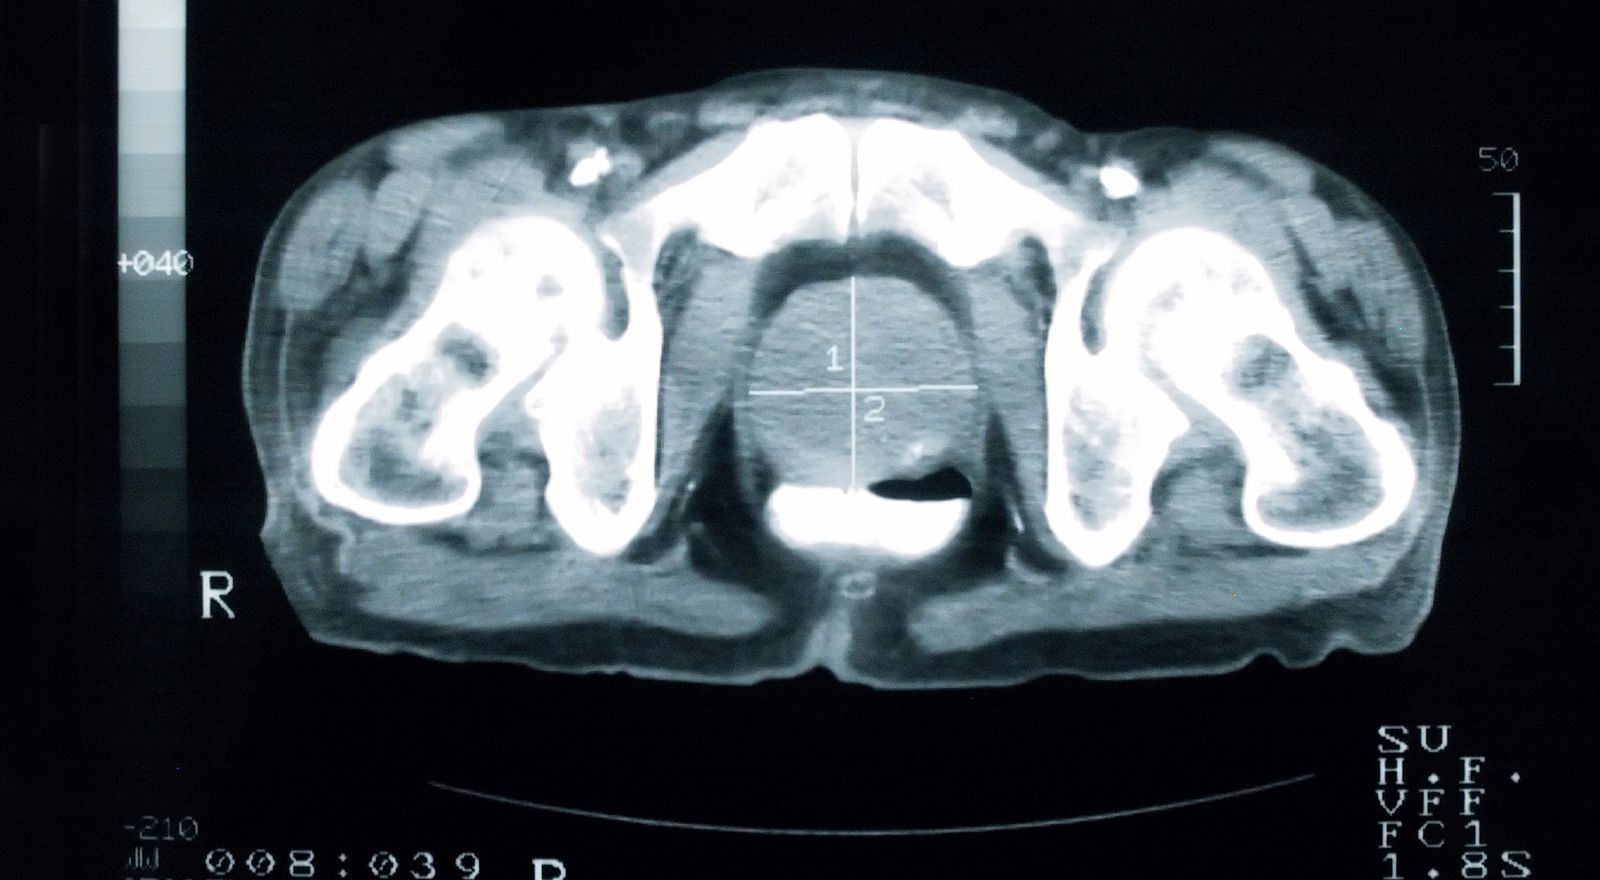

The FDA has approved a supplemental new drug application to add overall survival (OS) and other secondary end point data from the phase 3 ARAMIS trial (NCT02200614) to the prescribing information for darolutamide (Nubeqa) for the treatment of patients with nonmetastatic prostate cancer (nmCRPC).